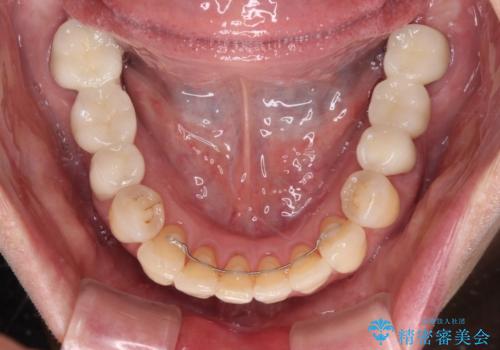

下顎と上顎臼歯部については矯正治療を行い、奥歯の欠損部位はオールセラミックブリッジを、その他の銀歯はセラミックインレーなどにより治療を行うこととしました。